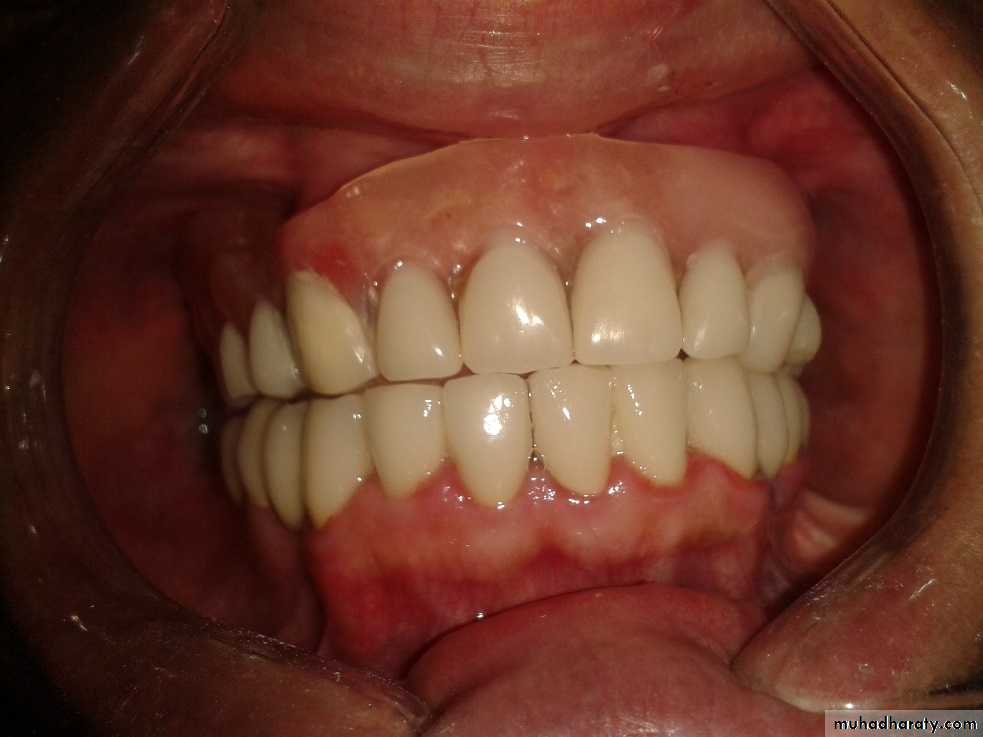

It is a tumor arising from embryonal cells of developing teeth. Although most forms of this tumor simulate other slow-growing benign tumors some can develop malignant tendencies.Patient may have few subjective symptoms during tumor growth. Enlargement of the tumor may expand the buccal, lingual or palatal bone plates. Tooth may be loosen and pressure symptoms may occur.

Ameloblastic fibroma and the ameloblstic adenoma are also tumors related to dental epithelium. These benign neoplasm grow slowly and expand the cortical plates of the jaws these tumors occur most frequently in the second and third decade of life and are painless in the early stages of growth. Surgical treatment is accomplished by complete local excision and cauterization